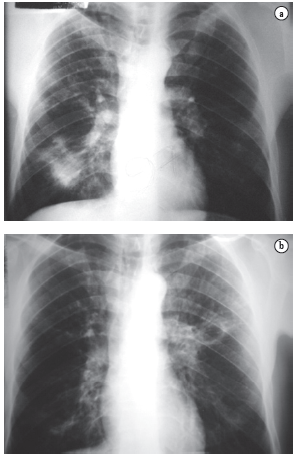

One case in particular seems to be illustrative of a true combination of PCM and TB. Eight years ago, the patient was definitively diagnosed with PCM through positive sputum smear testing for P. brasiliensis and was treated with trimethoprim-sulfamethoxazole for two years. The treatment was then suspended due to clinical improvement and negative serology. This patient again presented respiratory complaints five years after the end of the anti-PCM treatment, at which point he was diagnosed with TB (through positive sputum smear microscopy for acid-fast bacilli) and treated with Regimen I (rifampicin, isoniazid, and pyrazinamide). There was a good clinical response, and the patient was considered cured. Four months after the end of the anti-TB treatment, the patient again complained of fever, weight loss, mild productive cough, and dyspnea, Recurrence of PCM was confirmed (Figure 5), and the treatment with trimethoprim-sulfamethoxazole was restarted.